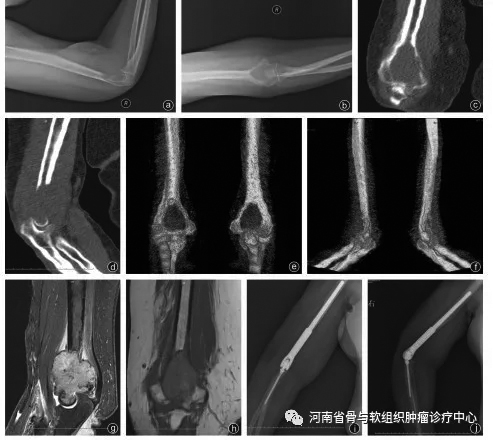

原发性恶性骨肿瘤会致残,甚至造成患者死亡。随着技术的发展,保肢治疗已成为原发性恶性骨肿瘤患者的主要手术方式。随着原发性恶性骨肿瘤的规范化治疗,这类患者的5年生存期已达到50%~80%。人工假体能够较快恢复骨骼的连续性和关节功能,得到了医务工作者的青睐,具有术后即刻稳定、患者可早期负重、短期和长期术后功能较好的优点。 下面,我向大家简单介绍一下目前临床上使用的人工假体。 定制型人工假体:此类假体在最初用于肿瘤切除后骨缺损的重建,需要术前根据患者的影像学检查结果进行个体化定制,术前需要反复测量数据,多次和工程师沟通;存在术中假体尺寸不合适,需要调整截骨范围,甚至无法完成手术的风险,现在较少使用。目前,定制型人工假体主要用于特殊人群(年龄小、无组配型人工假体、假体髓针过短而需要特殊设计者)和经济困难的患者,是组配型人工假体的一个补充。 组配型人工假体:随着定制型人工假体应用的增多和生物固定技术的发展,根据瘤段骨的特点术中组装合适规格的假体逐渐成为主流。主要优点包括可对多个组配模块进行术中调换组装,后期翻修时仅需更换受损部件。组配型人工假体目前较多地应用于肱骨近端、股骨近端和肿瘤累及膝关节面的患者。 可延长假体:可延长假体主要是为了解决儿童保肢术后双下肢不等长的问题而研发的。目前主要应用的是微创或无创可延长假体,适应证是:预计下肢短缩>3厘米,上肢短缩>5厘米,或者年龄<11岁的女孩和年龄<13岁的男孩。这类假体主要的远期并发症是无菌性松动。随着患儿身高的不断增长,骨骼的生长会使骨骼横径和髓腔横径增大。另外,患儿的依从性差,活动量大,因此松动率较高,待其成年后可更换为普通成人型人工假体。由于延长过程中多次手术造成的瘢痕,及延长后髌腱和股四头肌腱的相对短缩,容易造成关节活动受限。一般建议每次延长0.5厘米~1厘米。 半关节假体:为了避免损伤关节健侧骨骺,有的医院开始尝试在股骨远端和胫骨近端进行半关节置换,保留关节一侧的骨骺,可尽量减少肢体不等长的发生。术中需要精心设计假体长度和关节面大小,并保留和重建周围韧带,术后进行支具保护。经过患者较长时间的康复锻炼,仍可维持膝关节的稳定并取得较高的功能评分。 其他假体:随着对肿瘤生物学、精准截骨的设计和假体研究设计的进展,为了达到更好的功能重建的效果,有的医生会对患者进行带血管蒂和假体的复合创建,保留骨骺的假体重建和精准截骨后3D(三维)打印重建等。 (作者供职于河南省肿瘤医院)